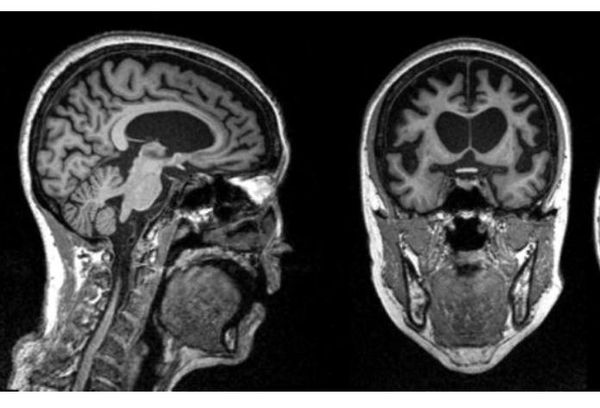

Что же касается инструментальных методов исследования, то всем пациентам с подозрением на болезнь Пика показано МРТ головного мозга, также при возможности целесообразно пройти ПЭТ-КТ. При этом заболевании выявляется диффузная атрофия лобных или лобно-височных отделов головного мозга. Этот признак относится к обязательным критериям для постановки диагноза. Он позволяет отличить болезнь Пика от других психиатрических (например, депрессии, биполярного расстройства, шизофрении) и неврологических заболеваний (болезни Паркинсона, деменции с тельцами Леви). Также КТ или МРТ помогут исключить такие причины симптомов, как патологические очаговые изменения (например, гематомы или участки повреждения после инсульта) и объёмные образования [9].

![МРТ головного мозга пациентки 50 лет с диагнозом болезнь Пика. На снимках прослеживается выраженная атрофия лобной и височной долей [2] МРТ головного мозга пациентки 50 лет с диагнозом болезнь Пика. На снимках прослеживается выраженная атрофия лобной и височной долей [2]](/media/bolezny/bolezn-pika/mrt-golovnogo-mozga-pacientki-50-let-s-diagnozom-bolezn-pika-na-snimkah-proslezhivaetsya-vyrazhennaya-atrofiya-lobnoy-i-visochnoy-dolyay-2_s.jpeg)

МРТ головного мозга пациентки 50 лет с диагнозом болезнь Пика. На снимках прослеживается выраженная атрофия лобной и височной долей [2]